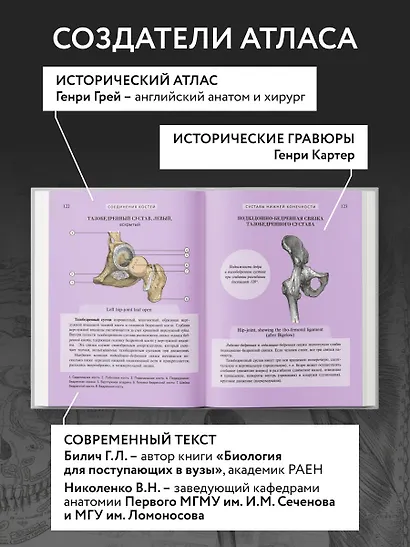

Билич Габриэль Лазаревич, Николенко Владимир Николаевич: Популярный атлас анатомии человека. Анатомия Грея. 200 классических иллюстраций

«Популярный атлас анатомии человека» — это оптимальный объем базовых знаний о строении человеческого тела. Созданная современными учеными-анатомами с использованием новейших данных, книга предлагает четко структурированную информацию, изложенную в 10 тематических главах по основным анатомическим системам.

Особую ценность изданию придают высококачественные репродукции классических гравюр из знаменитой «Gray's Anatomy» — самого известного англоязычного учебника по анатомии человека. Более 200 классических иллюстраций выполнены с безупречной детализацией благодаря современным полиграфическим технологиям. Винтажные гравюры XIX века сочетаются с удобным компактным форматом и ярким дизайном, что делает книгу одновременно эстетически привлекательной и практичной в использовании.

"Популярный атлас анатомии человека" — это доступное, красочное и информативное издание, содержащее основные сведения о строении человеческого тела. Написанный ведущими учёными-анатомами с учётом последних научных данных, атлас предлагает систематизированную информацию, разделённую на 10 глав по ключевым анатомическим системам. Книга сочетает в себе ясность изложения и высокое качество визуального материала: она проиллюстрирована классическими гравюрами из знаменитой "Анатомии Грея", что делает изучение анатомии наглядным и увлекательным. Удобный компактный формат практичен в использовании,а цветная печать изображений обеспечивает комфортное чтение и детальное рассмотрение иллюстраций из всемирно известного медицинского учебника.